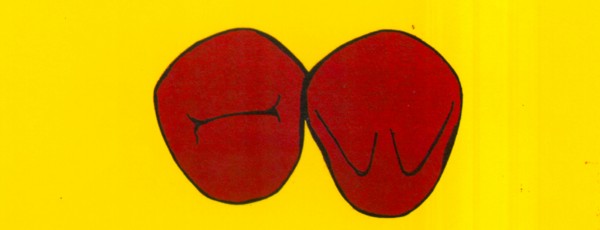

RESUMEN Más allá en el tiempo, respecto de las razones más frecuentes de fracasos como temperatura de fresado, infecciones, falta de fijación inicial, falta de higiene, etc., la OCLUSIÓN recibe sobre sí, la responsabilidad de la permanencia de la osteointegración, como así de la ortofunción del sistema todo. Sometimes ago,conserning the most frecuent reason of failures such as the strawberry action temperature, infections and lack of hygiene…etc.,the OCLUSION has itself the responsability af having the osteointegration well as the allsistem ortofunction . DESARROLLO La valoración de los fracasos en IMPLANTOLOGÍA es difícil de contabilizar sobre todo después del año, ya que el confort logrado por lo general, hace que el paciente realice correctamente sus primeros controles, y después; apoyado en su bienestar; intente subconscientemente olvidar ese período de su vida, que si bien le devolvió su capacidad masticatoria, fonética, social, etc., le ocasionara gastos, molestias, sufrimientos. … la APLICACIÓN de dichas fuerzas, requiere de una exactitud mucho mayor. Los esquemas propuestos a través de los años, no son muchos ni muy variados… I-Evitar las fuerzas tangenciales. II-Repartir las fuerzas lo máximo posible. Sin embargo, muchas veces se confunden los conceptos anteriores con criterios inexactos. Por ej: a-Reducción de las caras vestibulares y palatinas, aceptando que la menor superficie de intercontactos reduce la carga. b-Utilización de la Función de Grupo Posterior, en la creencia de que repartiendo el esfuerzo en las piezas posteriores, ganamos resistencia; a la potencia ejercida por los músculos. c-No permitiendo el contacto excéntrico de un canino implantado, para aliviarlo de las cargas laterales, sobre cargando de esta manera la tabla premolar-molar en el Lado de Trabajo. Algunos conceptos aislados, que forman parte de toda una filosofía de la Oclusión (OCLUSIÓN ORGÁNICA), sean tal vez de ayuda para echar luz sobre los preceptos anteriores. 1º-PROPORCIONES FUNCIONALES DE UN PAR OCLUSAL En la figura siguiente, observamos la relación final masticatoria de un PAR OCLUSAL: En el se ven los contactos puntiformes, producto del choque de superficies redondeadas contra superficies redondeadas («Solo pueden encontrarse en un punto» Ref: Principios Mecánicos Esferoidales.W.Mc.Horris.) Si Miramos con atención este tipo de contactos interoclusales, veremos que la superficie actuante es mucho menor que la superficie total de la cara oclusal: 45% (Fig.1) Por lo tanto, si no es por razones del Pilar de Emergencia para no crear un espacio biológico inadecuado… ¿POR QUÉ REDUCIR LA CARA OCLUSAL VESTÍBULO LINGUALMENTE? (Figs. 2-3-4-5) Si observamos con atención las figuras 2-3-4-5, veremos desde todos los planos , que el área contactante es muy reducida respecto del ancho oclusal total, siendo las fuerzas resultantes , AXIALES al eje implantario. 2º-FUNCIÓN DE GRUPO POSTERIOR. FUNCIÓN CANINA. Tres son las razones por las cuales nos inclinamos a la utilización de la Función Canina. En cambio, en el esquema de FUNCIÓN CANINA, podemos observar que el BRAZO DE POTENCIA, es prácticamente igual al de RESISTENCIA, equilibrando de esta manera la palanca y destruyendo mucho menos las estructuras de soporte(Interface I-H) (Fig. 7) Otra de las razones de peso en este tema es la DIFERENCIA DE ANGULACIÓN que existe entre la cara palatina del canino y las vertientes contactantes del sector premolar-molar. A MAYOR ANGULACIÓN, MENORES FUERZAS LATERALES(Perpendiculares al Plano), y por lo tanto , menor destrucción de la interface Hueso-Implante(Figs. 9-11). DIFERENCIAS EXCITATORIAS DE LOS GRUPOS MUSCULARES. Por último debemos considerar que el intercontacto dentario del sector anterior, estimula excitatoriamente a las fibras anteriores y verticales del temporal (Figs.12-13-14-15), mientras que los contactos posteriores lo hacen con la cincha pterigo-maseterina(Fig. 16-17-18-19) Por lo tanto ,si se comprende el fisiologismo de estos conceptos, es sencillo entender que la sobrecarga de los sectores posteriores es nocivo generando fuerzas tangenciales de Alto Potencial Patológico. 3º-FUNCIÓN DE GRUPO ANTERIOR Las ventajas de un Brazo de Resistencia mayor se acentúan cuando tenemos el esquema de FUNCIÓN DE GRUPO ANTERIOR. Además, debemos tener en cuenta que, durante la función de un Ciclo Masticatorio, es más importante la Desoclusión Final que la Desoclusión Inicial, ya que al ser más larga esta última, es durante el transcurso de su deslizamiento cuando se ejercen fuerzas laterales mayores(Fig. 21) A medida que la punta del canino inferior se acerca a la O.R.C., o sea al Punto de Contacto Intercanino, las fuerzas laterales disminuyen en virtud del acortamiento del brazo de potencia de la palanca, hasta que, al terminar su recorrido, la fuerza es proyectada axialmente sobre el eje del canino superior, debido a que, al margen de la intensidad que la fuerza trae durante el cierre, la dirección de la misma «apunta» en esa dirección. Por eso decimos que los caninos Axializan el Ciclo Masticatorio. Si estamos imitando en lo posible a la naturaleza, no olvidemos este detalle que los dientes naturales provéen, para evitar las fuerzas laterales del canino a la hora de realizar la supraestructura coronaria del mismo. Es ahora menester acentuar que la problemática concreta se manifiesta, no durante la función, sino durante la PARAFUNCIÓN… Cuando estudiamos recorridos de la Dinámica Mandibular, desde el conocido Bicuspoide de Posselt hasta cualquiera de los registros pantográficos, estamos invirtiendo la dirección del movimiento… A.- El primer premolar es el más anterior de la tabla oclusal posterior. Por lo tanto el brazo de resistencia es el mayor de dicha tabla. B.- El lateral, como parte del grupo anterior, cuenta con un empotramiento tipo «clavo largo», y el interseptum lateral -canino, que se opone a la fuerza, es mucho más grueso que la tabla vestibular del primer premolar(Fig.23) C.- Condiciones, las dos anteriores que se favorecen considerablemente, si al enfundar el lateral se logra junto al central una Función de Grupo Anterior. D.- De manera más artificiosa, la instalación de una placa de relajación, soluciona durante la noche lo nocivo de las fuerzas laterales. Veamos un par de casos, como ejemplo de lo dicho: Paciente de 54 años que se presenta a la consulta portando prótesis completa superior y antagonista natural que soporta fundas de porcelana. Obsérvese la función de grupo posterior ejercida, y las consecuencias de la misma: Otro paciente que presenta fractura de la cúspide fundamental de un onlay de porcelana antagonista de cinco piezas implantadas (Fig.27). Radiográficamente se observa la desinserción de uno de sus abuttments cementados (Fig.28). En el Lado de Trabajo (LT), no existe el canino encargado de desocluir la zona afectada (Figs.29-30) Como corolario, cabe entonces una pregunta: ¿Es el Implante en el canino quien debe preservar de patología oclusal al resto del sistema…. ¿Es el Implante…un medio…o un fín? BIBLIOGRAFÍA 1- Dibujos tomados del libro del mismo autor: «OCLUSIÓN ORGÁNICA… UN CAMINO HACIA LA REHABILITACIÓN ORAL»(en preparación) 2- «NEUROFISIOLOGÍA DE LA OCLUSIÓN» 3- «OCLUSIÓN Y FUNCIÓN» 4- «FUNDAMENTOS, TÉCNICAS Y CLÍNICA EN REHABILITACIÓN BUCAL» 5- «OCLUSIÓN Y REHABILITACIÓN» 6- «DISFUNCIÓN TEMPOROMANDIBULAR» 7- «PROCEDIMIENTOS CLÍNICOS Y DE LABORATORIO DE OCLUSIÓN ORGÁNICA» 8- «ESTUDIO ELECTRÓNICO DEL MOVIMIENTO MANDIBULAR» 9- «OCLUSIÓN: CONCEPTO PARA EL CLÍNICO» 10- «IMPLANTOLOGÍA CONTEMPORÁNEA» 11- «OCLUSIÓN Y DIAGNÓSTICO EN REHABILITACIÓN ORAL» 12- «PRINCIPIOS DE OCLUSIÓN»

Un minucioso examen de la anatomía dentaria, nos muestra que el vínculo entre el canino superior y el primer premolar, es afectado por una Ferulización Natural, que los solidariza de la siguiente manera (Fig. 22):